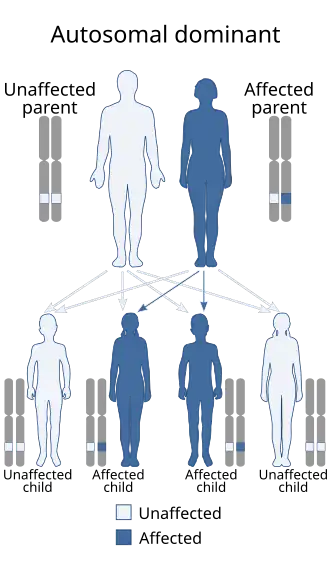

| Causes | Genetic (autosomal dominant)[1] |

MFS is caused by a mutation in FBN1, one of the genes that make fibrillin, which results in abnormal connective tissue.[1] It is an autosomal dominant disorder.[1] In about 75% of cases, it is inherited from a parent with the condition, while in about 25% it is a new mutation.[1] Diagnosis is often based on the Ghent criteria,[9] family history and genetic testing (DNA analysis).[2][4][3]

Each parent with the condition poses a 50% risk of passing the genetic defect on to any child due to its autosomal dominant nature. Most individuals with MFS have another affected family member. About 75% of cases are inherited.[1] On the other hand, about 15–30% of all cases are due to de novo genetic mutations;[29] such spontaneous mutations occur in about one in 20,000 births. Marfan syndrome is also an example of dominant negative mutation and haploinsufficiency.[30][31] It is associated with variable expressivity; complete penetrance has been definitively documented.[32]